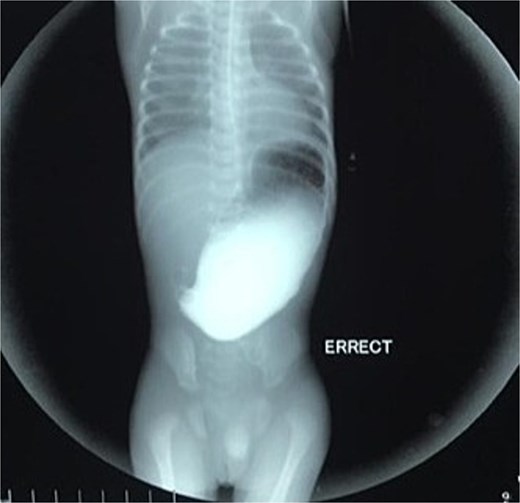

On the ninth day of life, the infant underwent exploratory laparotomy, which confirmed the diagnosis of Type I PA. A markedly dilated stomach with collapsed distal bowel was observed (Fig. 3). Pyloroplasty with transanastomotic nasoduodenal tube placement was performed (Figs 4 and 5). The nasoduodenal tube served as an alternative to parenteral nutrition, which was unavailable in our setting.

Surgical intervention is the mainstay of treatment for PA, and the choice of procedure depends on the anatomical type of atresia. In our case, pyloroplasty was performed for Type I PA, which involves the excision of the obstructing diaphragm and reconstruction of the pyloric channel. This procedure has been widely reported in the literature with favorable outcomes, particularly in isolated cases of PA [10]. The use of a transanastomotic nasoduodenal tube, as employed in our case, is a practical alternative to parenteral nutrition in resource-limited settings where advanced nutritional support may not be available [11].